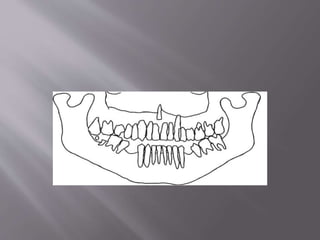

 A panoramic radiograph and tracing together

with the periapical radiographs revealed extensive

apical root resorption in all teeth except teeth 18,

23, 31–34, 37and 41–44. Eighteen teeth had apical

root resorption, mostly in the maxilla

 On the basis of the history, clinical examination and

radiographic evaluation, a diagnosis of multiple

idiopathic apical root resorption was made.